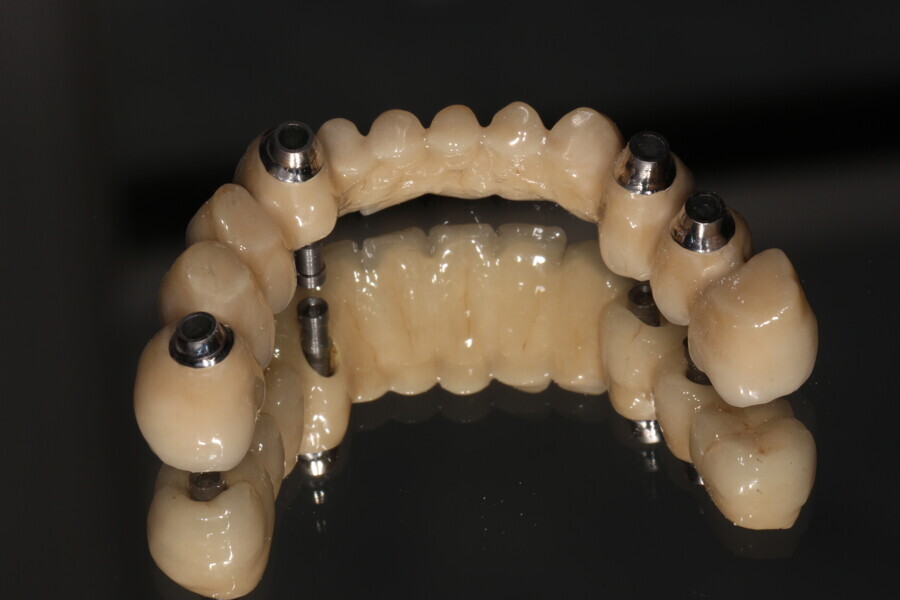

Fig. 12: Crowns on printed model.